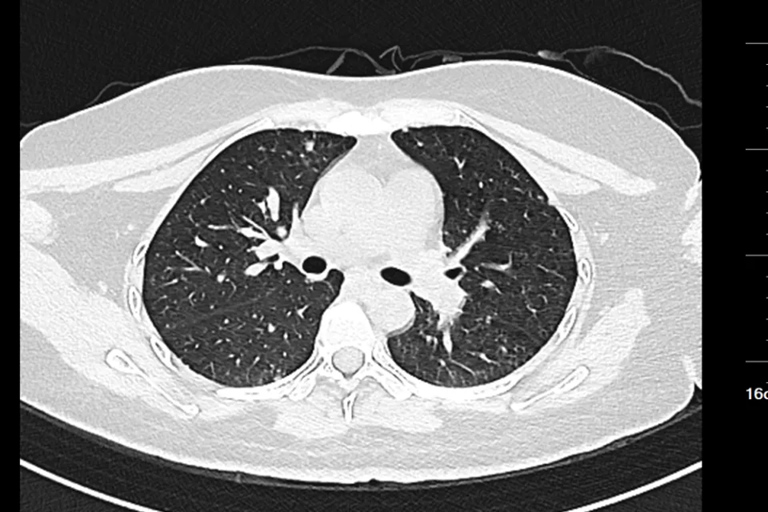

Hình ảnh chụp CT của nữ sinh 20 tuổi

Gần đây, một phụ nữ ngoài 20 tuổi đến khám tại Bệnh viện Nhân dân Đông Hoản (Quảng Đông, Trung Quốc) vì phát hiện khối u ở cổ trái trong khoảng một tuần.

Trước đó, cô cảm thấy vùng cổ đau nhẹ và sờ thấy một khối cứng kích thước gần bằng quả trứng gà. Khối u ấn vào có cảm giác đau nhưng không đỏ, không sưng. Điều đáng nói là cô không hề có triệu chứng tiêu hóa rõ ràng như đau bụng, đầy hơi hay sốt, ăn uống và đại tiện vẫn bình thường.

Sau khi nhập viện để kiểm tra toàn diện, bác sĩ tiến hành nội soi dạ dày và sinh thiết hạch cổ . Kết quả giải phẫu bệnh cho thấy bệnh nhân mắc ung thư biểu mô tuyến kém biệt hóa , trong đó có thành phần ung thư tế bào nhẫn – một dạng ung thư dạ dày ác tính cao.

Chụp CT cho thấy khối u đã di căn toàn thân , không còn chỉ định phẫu thuật. Các bác sĩ chỉ có thể đề nghị điều trị bằng hóa trị, xạ trị hoặc liệu pháp miễn dịch nhằm kiểm soát bệnh.